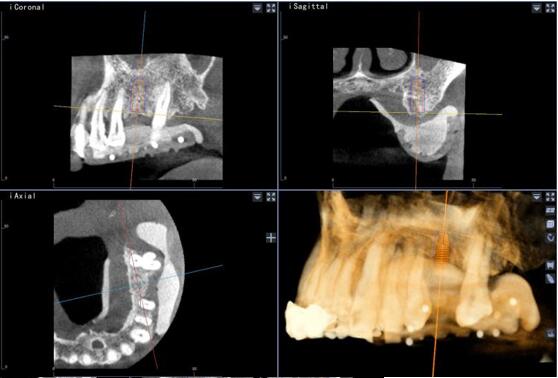

該系統(tǒng)用于口腔種植手術(shù)的術(shù)前計(jì)劃和術(shù)中引導(dǎo),通過對三維醫(yī)學(xué)影像的虛擬可視化應(yīng)用,采用專門的種植手術(shù)方案規(guī)劃軟件在三維模擬環(huán)境中進(jìn)行合理的種植方案設(shè)計(jì),結(jié)合精確的紅外光學(xué)定位技術(shù),實(shí)現(xiàn)手術(shù)器械、醫(yī)學(xué)影像和人體空間位置的融合。整個(gè)手術(shù)過程系統(tǒng)實(shí)時(shí)呈現(xiàn)病人解剖結(jié)構(gòu),全程監(jiān)控種植位點(diǎn)、角度、深度,從而實(shí)現(xiàn)精確種植。

術(shù)前種植體規(guī)劃

術(shù)中實(shí)時(shí)導(dǎo)航

術(shù)中實(shí)時(shí)種植導(dǎo)航

術(shù)后精度驗(yàn)證

種植體類 型植入點(diǎn) 末 端角 度

26 計(jì)劃<->實(shí)際 0.88 0.96 2.68